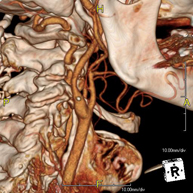

- Angio – Supra-Aortic Trunk CT

Radiological test that provides high definition anatomical images of the carotid arteries of the neck using CT (Computed Tomography) equipment and the injection of an intravenous contrast agent. The images are then reconstructed in three dimensions (3D). Indicated for: acute cerebral vascular accident, transient vascular accident, carotid bruit.